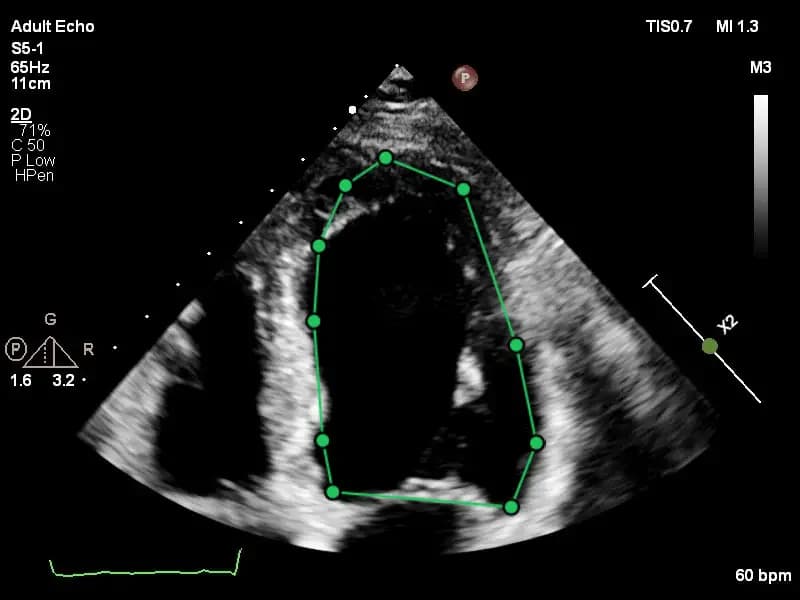

Practice with anonymized echocardiography cases from real clinical encounters.